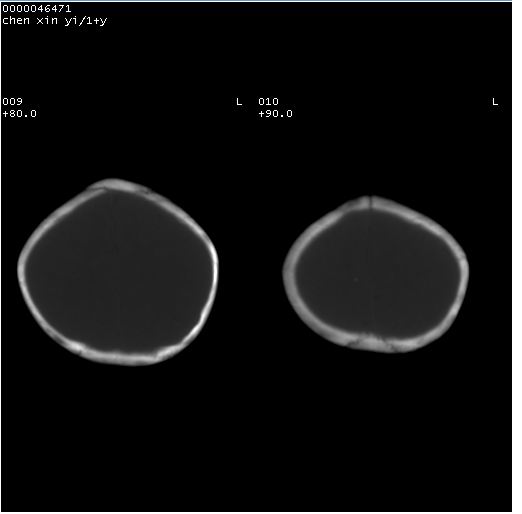

以下是引用zhangzhongshou在2008-4-9 12:54:00的发言:[br]请结合病史,有以下可能1、炎性肉芽肿钙化(含结核)2、寄生虫钙化(含脑囊虫)3、其他良性钙化性病变